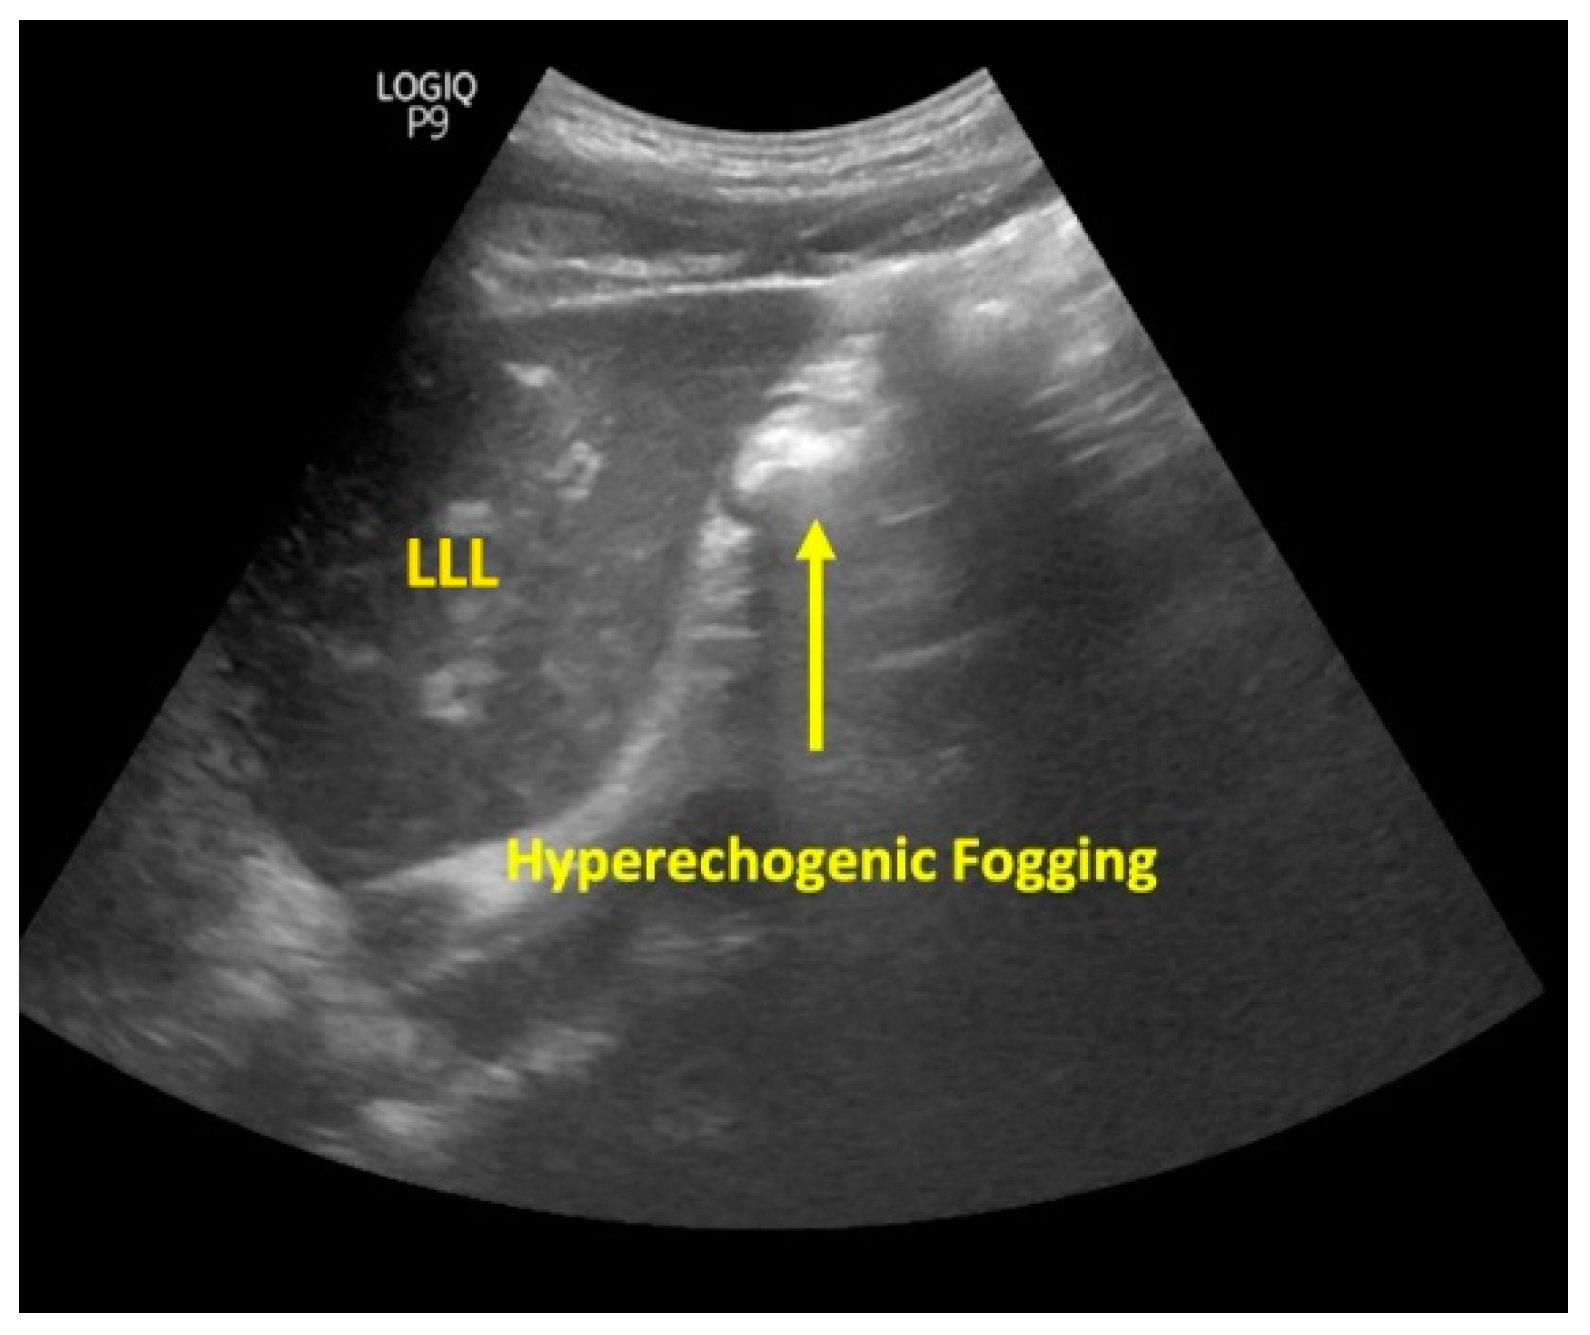

2. Materials and Methods